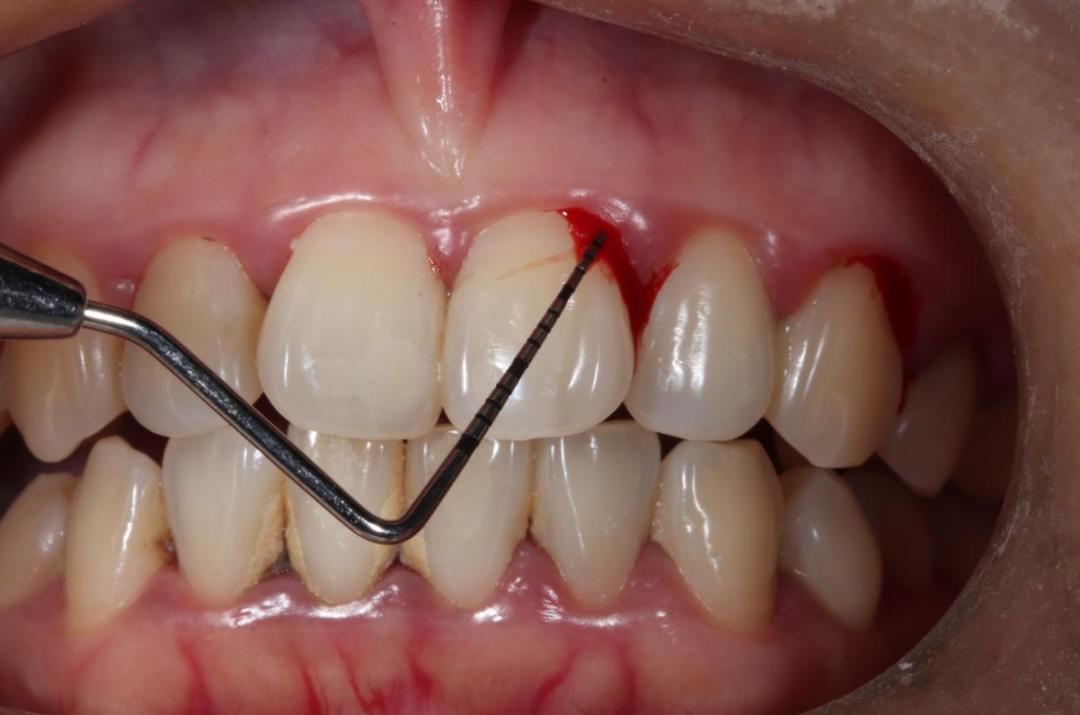

牙线清理牙缝时出血较多,可能是有牙结石,需要牙周检查和治疗。

探诊时牙龈出血